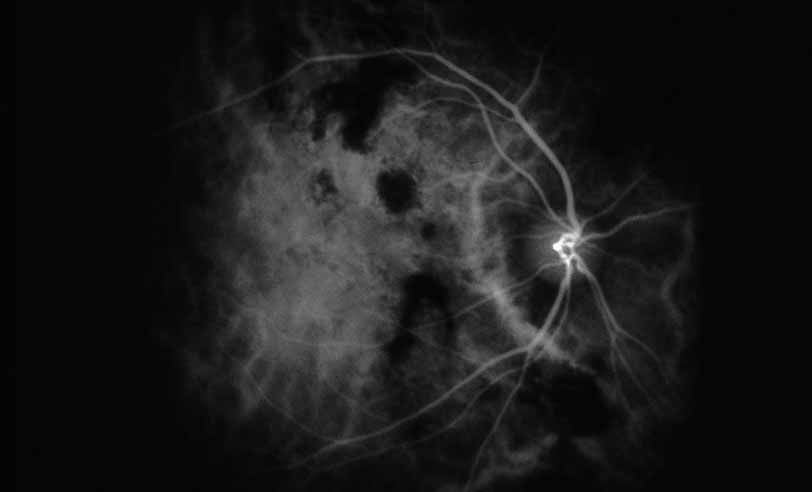

Fig. 28 Serpiginous choroiditis. ICG angiography early frame shows multiple hypofluorescent spots in the location of the lesions seen on color photography.